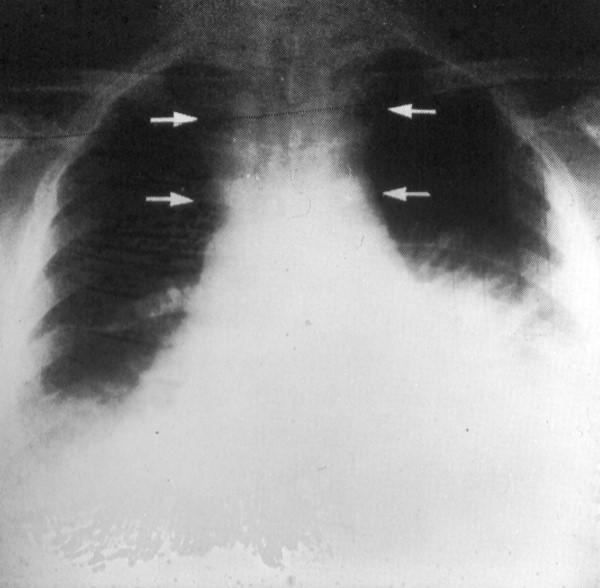

Cutaneous anthrax (left image) and inhalation anthrax with pneumonitis and hemorrhagic mediastinits (right image, arrows). The inhaled organism typically travels via lymphatics to involve the mediastinum. This patient also had sepsis and meningitis - the latter accounting for his positive Kernig's sign.